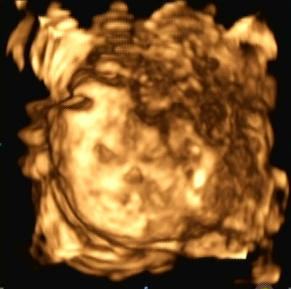

Ein zunächst durchgeführtes CTG war unauffällig. Im Rahmen der sonografischen Untersuchung zeigte sich der Fötus soweit beurteilbar zeitgerecht entwickelt. Dennoch konnte ein Anhydramnion festgestellt werden(Abb. 1, 2), weshalb auch kein fetales Gesicht darstellbar war (Abb. 3).